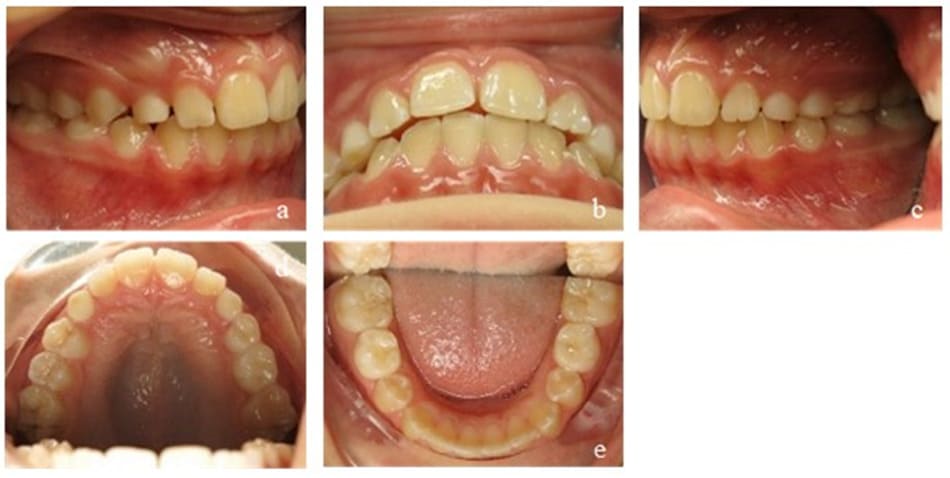

This patient was transferred to our orthodontic office by her speech-therapist at the age of 6. During initial diagnosis, a unilateral posterior cross bite on the right side and an anterior open bite of 3 mm were apparent. Accordingly, the upper arch was too narrow and needed further transversal development. Mild crowding in the lower front segment and an exaggerated Wilson’s curve of the lower permanent and deciduous molars could be seen. The dental situation confirmed the myofunctional diagnosis of a habitual open mouth posture, infantile swallowing, a low resting position of the tongue and enlarged palatine tonsils. Nasal polyps had already been removed at an earlier stage (Figure 10).

Figure 10: Case 2. Initial findings. En face (a, b) and profile of the patient (c). Frontal view of the occlusion (e), occlusion right (d) and left (f). Upper (g) and lower arch (h). Initial Panoramic x-ray (i).

Our initial orthodontic goal was the posterior cross bite elimination by maxillary expansion to create enough space for the tongue. The second goal was to straighten up the lower molars and to close the anterior open bite. Myofunctional goals comprised the establishment of nasal breathing, mature swallowing, and the physiological resting position of the tongue.

After the first treatment phase, the posterior cross bite was corrected and the anterior open bite reduced, but still remained present. The patient adapted the mature swallowing pattern rather quickly, but an interdental lisp remained and showed extensive tongue movement while wearing the EGA. The strength of the tongue was still low (Figure 11). The appliance of choice for the second phase was a Bionator instead of an EGA, because a Bionator allows speaking and can therefore be worn for more hours during the day. We controlled compliance with a Theramon® chip (MC Technology GmbH, Hargelsberg, Austria). The tongue movements calmed down and its strength increased while the open bite was further reduced to 1 mm. The maxillary transversal width was successfully retained. Mouth breathing could still be observed at times (Figure 12).

Figure 11: Case 2. Interims findings after 6 months of treatment. Frontal view of the occlusion (b), occlusion right (a) and left (c). Upper (d) and lower arch (e).